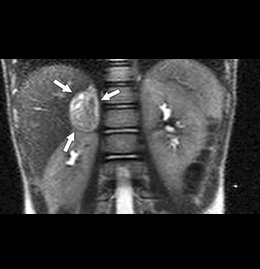

Detección de Feocromocitoma MIBGI131

Detección de tumores renales, para la localización de tumores derivados de la cresta neural y para el tratamiento de feocromocitomas malignos.

La metaiodobenzilguanidina marcada con I 131 (MIBG I131) es un análogo estructural de la hormona adrenérgica norepinefrina que se utiliza para la localización de tumores derivados de la cresta neural y para el tratamiento de feocromocitomas malignos.

Aunque el número de pacientes tratados es pequeño, en la literatura revisada se dispone de datos acerca de la inducción de remisiones objetivas y de la reducción de la actividad hormonal, consiguiendo respuestas sintomáticas. Sin embargo, la reducción del tamaño tumoral sólo se ha descrito en algunas ocasiones y casi nunca en presencia de metástasis óseas.